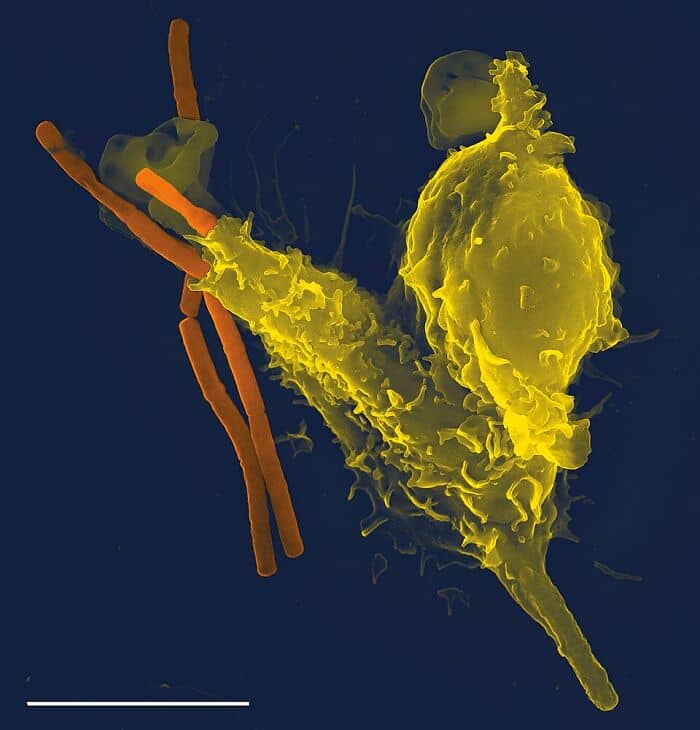

That your own immune system can destroy your body.

uhMothaWasAHamsta:

My immune system went after my kidneys. Now I’m on dialysis and hoping to get on the transplant list. They put me on chemo to destroy my immune system just to make it stop so now it takes me forever to heal, if I ever do.